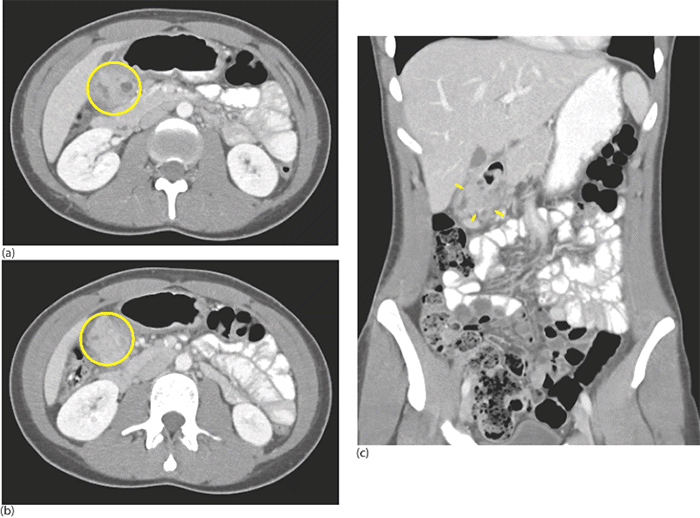

An 18-year-old woman presented with nausea, nonbilious, nonbloody vomiting, and poorly localized abdominal pain with diffuse tenderness. Laboratory workup revealed mild leukocytosis. Given a history of contact with sick individuals, a provisional diagnosis of viral gastroenteritis was made, and she was discharged. However, persistent symptoms prompted her return to the emergency department the following day. A CT scan suggested a 4.3 × 5.7 cm mass near the pylorus/duodenum (Figure 1).

Figure 1. Abdominopelvic CT Imaging of Periduodenal Mass. Published with Permission

Panel A (axial view, cephalad perspective) and Panel B (axial view) show a mass encircling the pylorus and duodenum (yellow circle). Panel C (sagittal view) highlights the mass with yellow arrows. However, the CT findings were inconclusive, and the differential diagnosis included duodenal ulcer disease with penetration, leiomyoma, atypical gastrointestinal stromal tumor (GIST), focal pancreatitis, or annular pancreas